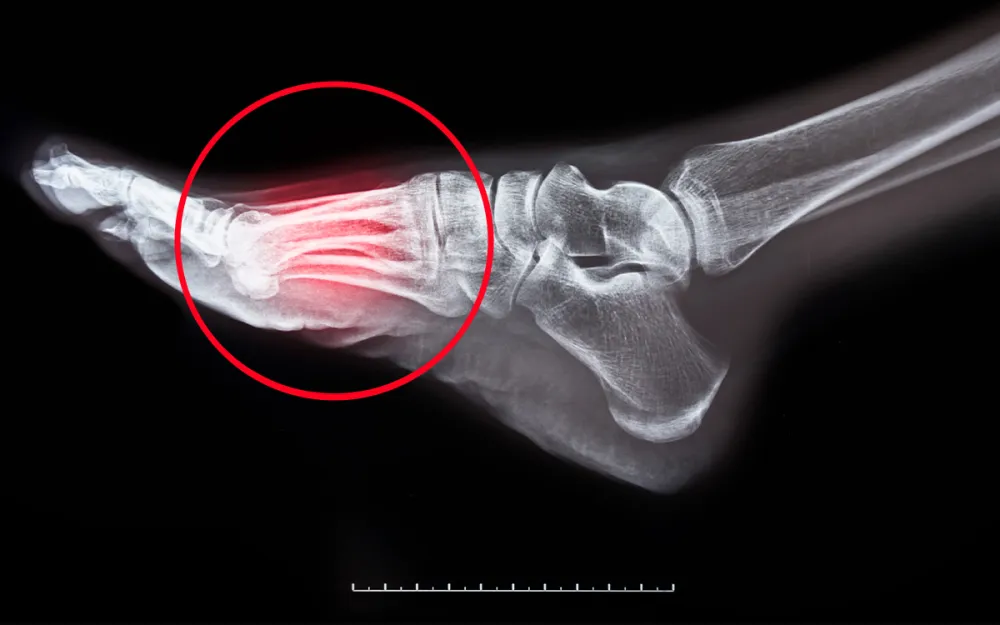

Dr. Sarah Weber hatte an diesem Tag nicht auf einen Durchbruch gehofft. Nach 15 Jahren als führende Physiotherapeutin in München dachte sie, sie hätte jede erdenkliche Lösung für Fußschmerzen gesehen. Ihre Praxis war monatelang im Voraus ausgebucht, da ihre Patient:innen verzweifelt auf der Suche nach Linderung bei chronischen Schmerzen, Plantarfasziitis und nachlassender Beweglichkeit waren.

„Ich habe ein beunruhigendes Muster bemerkt“, erinnert sie sich. “Meine Patient:innen verspürten eine vorübergehende Linderung, kamen aber immer wieder.“

Schlimmer noch, sie entwickelten neue Probleme:

• Chronische Knieschmerzen

• Hüftprobleme

• Komplikationen im unteren Rückenbereich

Herkömmliche Einlagen und Orthesen konnten das Problem nicht lösen. Sie verschleierten tiefere Probleme.